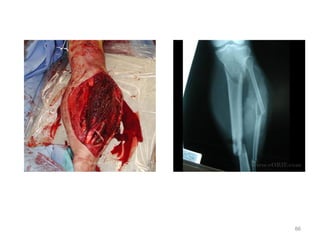

86

Disability

Unable to move right leg

Exposure

Open wound with bone exposed

• Secondary survey

– Pulseless limb

• How do you manage?

87

• Control bleeding

• Control pain

• Reduce

• splint

• Check NV

• Tetanus

• Abx